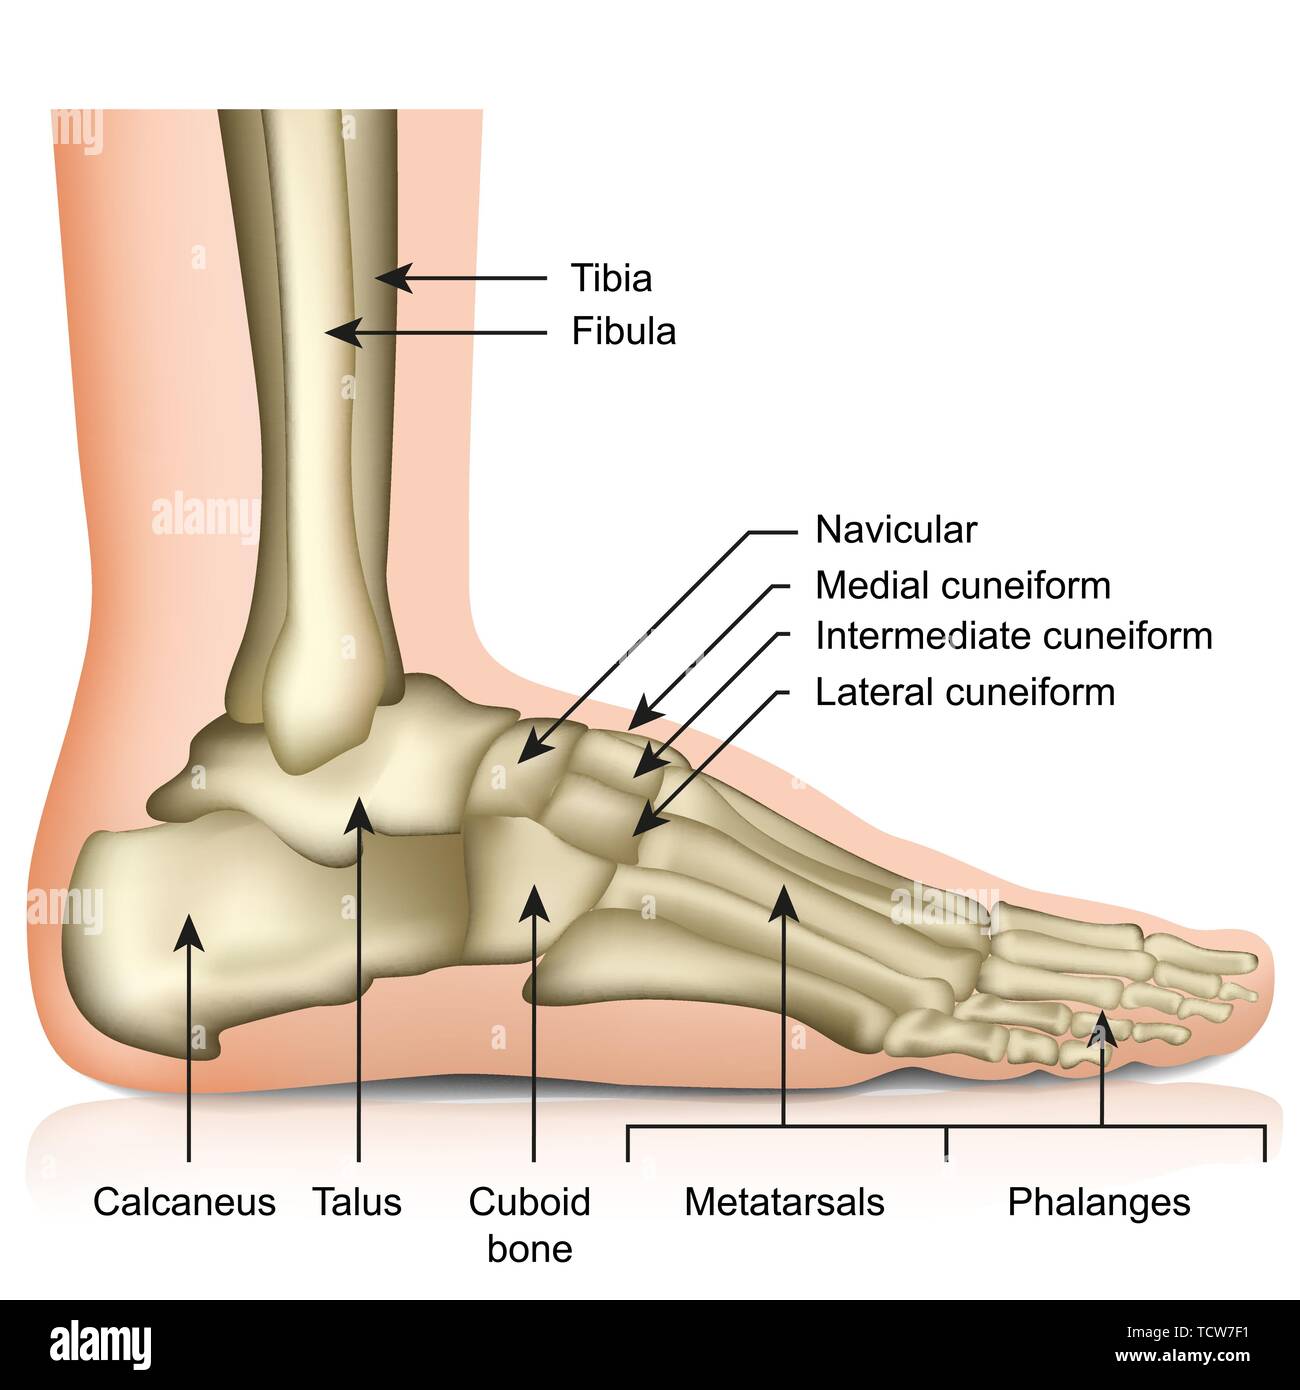

Foot Bones. Anatomy Of The Skeletal System Of The Human Legs And Feet

www.alamy.itBones Of Human Foot With Labels On White Background — Phalanx, Fibula

www.alamy.itBones Of Human Foot With Labels On White Background — Phalanx, Fibula

focusedcollection.comfoot bones human labels background fibula

focusedcollection.comfoot bones human labels background fibula